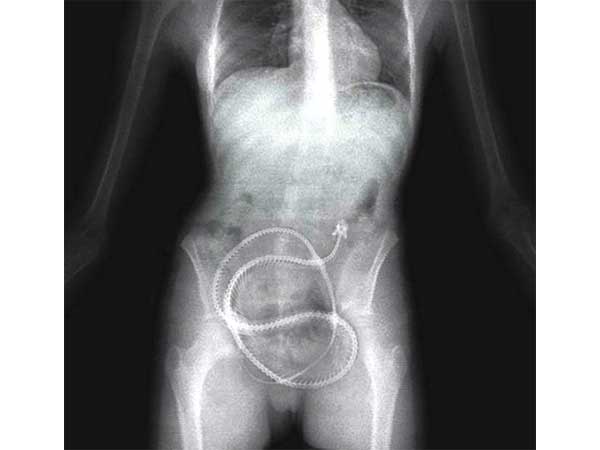

ಮಾದಕ ಪದಾರ್ಥಗಳು

ಮಾದಕ ಪದಾರ್ಥಗಳನ್ನು ಕಳ್ಳಸಾಗಣೆ ಮಾಡುವ ಸಾಮಾನ್ಯವಾದ ಈ ವಿಧಾನದಲ್ಲಿ ಹೊಟ್ಟೆಯಲ್ಲಿ ಕರಗಲಾರದ ರಬ್ಬರಿನಂತಹ ವಸ್ತುವಿನಿಂದ ಚಿಕ್ಕ ಕ್ಯಾಪ್ಯೂಲುಗಳನ್ನು ತಯಾರಿಸಿ ಇದರಲ್ಲಿ ಮಾದಕ ಪದಾರ್ಥ ತುಂಬಿ ನುಂಗಿ ಬಿಡುತ್ತಾರೆ. ವಿಮಾನದ ಪ್ರಯಾಣದ ಬಳಿಕ ಬಹಿರ್ದೆಶೆಯಲ್ಲಿ ಜೀರ್ಣಗೊಳ್ಳದೇ ಹೊರಬಂದ ಈ ಗುಳಿಗೆಗಳನ್ನು ಮತ್ತೆ ಸಂಗ್ರಹಿಸುತ್ತಾರೆ. ಮಲೇಶ್ಯಾದಲ್ಲಿ ಇದೇ ವಿಧಾನವನ್ನು ಅನುಸರಿಸಿ methamphetamine ಎಂಬ ಮಾದಕ ಪದಾರ್ಥವನ್ನು ಕಳ್ಳಸಾಗಣೆಗೊಳಿಸಲು ಯತ್ನಿಸುತ್ತಿದ್ದ ನೈಜೀರಿಯಾದ ನಾಗರಿಕರೊಬ್ಬರನ್ನು ಬಂಧಿಸಿ ಅವರಿಂದ 52 ಗುಳಿಗೆಗಳನ್ನು ಸಂಗ್ರಹಿಲಾಯಿತು.